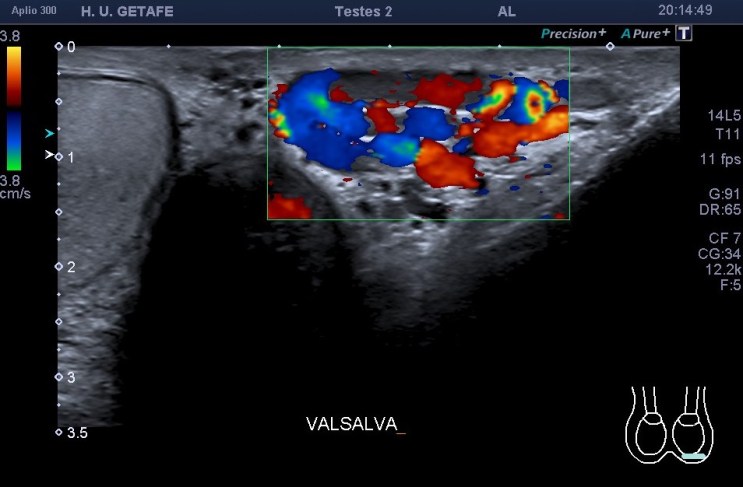

Repasa conmigo la anatomía en la imagen 1, te señalo el hallazgo que me llamó la atención. En la imagen 2 y 3 hay varicocele. De la 4 a la 7 el estudio dirigido al vaso central, hipoecogénico y serpenteante correspondiente a la malformación, básicamente deducido por su ausencia total de vascularización tanto en el doppler color como en el doppler power o modo angio.